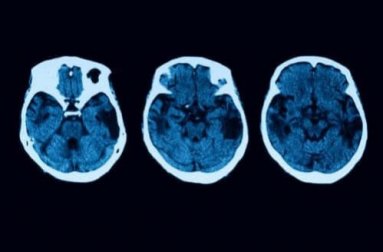

Esses testes para realizar um diagnóstico correto não param aqui. Para esclarecer qualquer dúvida, serão realizados testes neurológicos, incluindo ressonância magnética e tomografia. Se tudo indica que estamos lidando com um caso de atrofia cortical posterior, existem diferentes tratamentos aos quais um paciente pode optar.